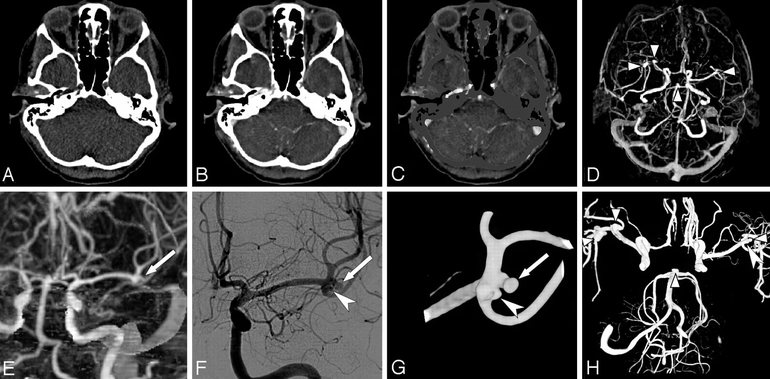

После анализа ангиограммы врач формирует соответствующие выводы. В норме костная ткань отображается белым цветом, а ликвор и здоровые сосуды — черным. При отсутствии патологий сосудистая система напоминает дерево с множеством крупных и мелких ветвей, а контрастное вещество равномерно распределяется по ней. Данное исследование помогает выявить различные отклонения, однако некоторые заболевания встречаются наиболее часто.

Внутричерепные гематомы, возникающие в результате травм головы, резкого повышения артериального давления или других факторов, хорошо видны на снимках. Контрастное вещество скапливается вокруг этих образований, что облегчает их обнаружение. Обычно у пациента наблюдаются и другие симптомы, поэтому ангиография используется для подтверждения диагноза и оценки размеров гематомы.

Холестериновые бляшки и тромбы на стенках сосудов также четко визуализируются. Пораженные участки сосудов могут быть утолщены, но их просвет сужен. Опасность таких заболеваний заключается в том, что у пациента могут отсутствовать какие-либо симптомы.

Расслоение стенки сосуда представляет собой крайне серьезное состояние, особенно если затрагиваются крупные вены или артерии. На рентгеновских снимках данная патология легко определяется.